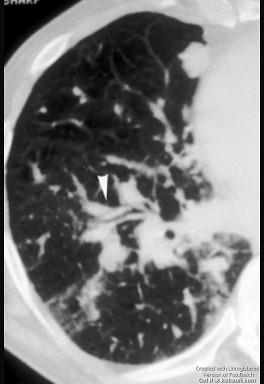

问题 62岁,女,咳嗽胸闷咯血1天,1年前行宫颈癌手术,请结合CT检查图,选出最可能的诊断 ( )

选项 A.错构瘤 B.肺转移瘤 C.结节病 D.淋巴结核 E.真菌病

答案 B